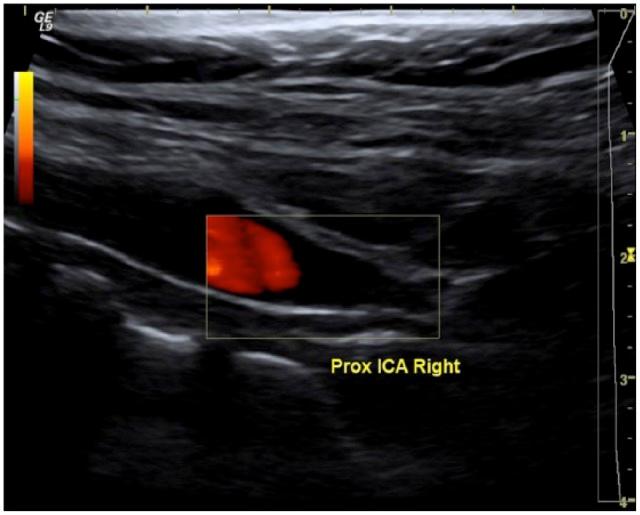

Carotid stump syndrome is defined as the persistence of retinal or cerebral ischaemic events with complete occlusion of the ipsilateral internal carotid artery. The aim of this retrospective cases series was to assess the outcomes for patients with carotid stump syndrome managed with surgical intervention. A series of 11 cases of carotid stump syndrome in nine patients presented to our tertiary vascular centre from October 2004 to February 2016. Indications for intervention were amaurosis fugax, transient ischaemic attacks and stroke. In total, 11 procedures were performed on nine patients including carotid angioplasty and stenting or carotid endarterectomy with patching. The mean follow-up period was 56.6 months. One patient suffered a myocardial infarction 30 days, post-operatively, and one patient was lost to follow-up. In the remaining seven patients, there was a complete resolution of symptoms. There were no incidents of death, stroke, cranial nerve injury, wound haematoma or procedural bleeding. Surgical exclusion of carotid stumps combined with dual antiplatelet agents was found to be a safe and effective treatment method for carotid stump syndrome.

颈动脉残端综合征的定义为同侧颈内动脉完全闭塞时视网膜或脑部缺血事件持续存在。本回顾性病例系列的目的是评估接受手术干预治疗的颈动脉残端综合征患者的治疗效果。2004年10月至2016年2月期间,9例患者中的11例颈动脉残端综合征病例被送至我们的三级血管中心。干预指征为一过性黑矇、短暂性脑缺血发作和中风。总共对9例患者进行了11次手术,包括颈动脉血管成形术和支架置入术或颈动脉内膜切除术加修补术。平均随访期为56.6个月。1例患者术后30天发生心肌梗死,1例患者失访。其余7例患者症状完全缓解。未发生死亡、中风、颅神经损伤、伤口血肿或手术出血事件。发现手术切除颈动脉残端联合双联抗血小板药物是治疗颈动脉残端综合征的一种安全有效的方法。